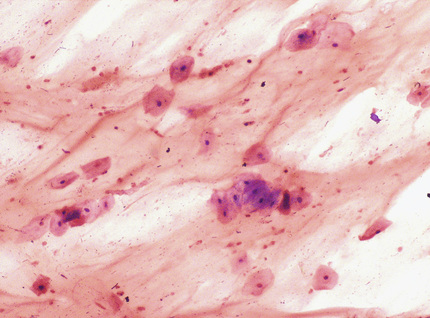

To detect C. trachomatis, a smear prepared directly from conjunctival scrapings may be stained with Giemsa stain and examined for epithelial cells with basophilic intracytoplasmic inclusions diagnostic of C. trachomatis, or preferably with monoclonal antibodies, which are more sensitive and specific than Giemsa. For optimal results with the direct fluorescent antibody test, the collection kit provided by the manufacturer should be used (see Chapter 56). The swab is rolled across the surface of the glass slide provided, the material is fixed, and the slide is transported promptly to the laboratory and held at room temperature or refrigerated for a short time. Slides are stained according to the manufacturer's directions and examined with a fluorescent microscope for elementary bodies (see Chapter 56). Specimens containing fewer than 10 columnar or metaplastic squamous cells are considered inadequate, and results should be reported as inconclusive, with an explanation, and another specimen should be requested. Culture is the reference method for detection of C. trachomatis and should be performed when a diagnosis of chlamydial conjunctivitis is strongly suspected and the direct fluorescent antibody test is negative.